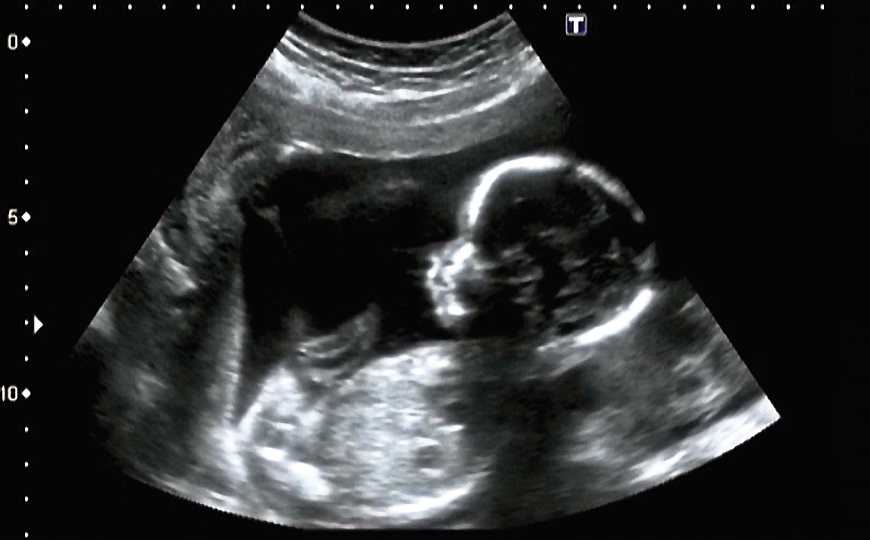

Для полноценного развития и выживания ребенка, находящегося в утробе матери, очень важна целостность плодных оболочек. Инфекции или травмы могут их повреждать, что очень опасно для плода. В настоящее время в клинике не существует методов восстановления плодных оболочек.